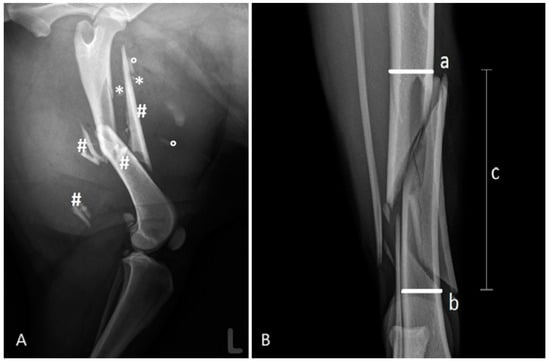

Figure 1. (A): Left femur of a 5-year-old female Collie—small (*), medium (°), and large (#) fragments. (B): Proximal (a) and distal (b) boundaries of the fragment zone (c) using an example of a canine tibia.